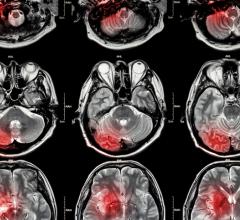

Jan. 27, 2026 — Researchers at the Icahn School of Medicine at Mount Sinai, in collaboration with other leading ...